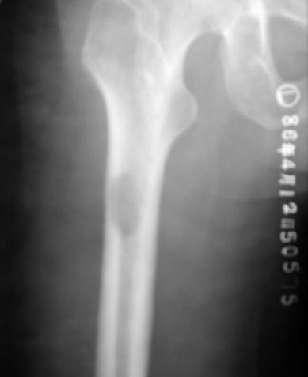

股骨头骨骺缺血性坏死:骨骺变小、碎裂变形,颈短粗,头向外移,内侧间隙增宽。

成人股骨头缺血性坏死:股骨头变形,增骨质生硬化囊变并存;左侧间隙变窄,右侧间隙正常。关节间隙变窄,退行性骨关节病,股骨头呈磨菇头状变形